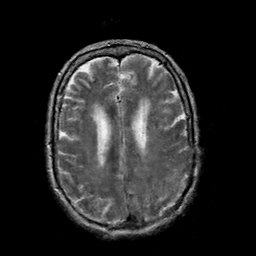

In this paper, we propose a bidirectional learning model, known as dual contrast cycleGAN (DC-cycleGAN), for medical image synthesis from unpaired data. Specifically, a dual contrast (DC) loss is formulated that leverages the advantage of samples from the source domain as negative samples to indirectly build constraints between real source and synthetic images via discriminators, and synthesize images more related to the target domain by enforcing the synthetic images to fall far away from the source domain. In addition, structural similarity index (SSIM) [35] and cross-entropy (CE) [48] are integrated into the DC-cycleGAN structure to avoid disappearing gradient information that is caused by a mean absolute error (MAE) and synthesizing irrelevant images. SSIM considers luminance [35] and CE converges fast as its back-propagation error is less than MSE [28]. As can be seen in Figs. 1 and 2, using SSIM and CE with dual contrast can generate more clear and accurate MR images as compared with that of MAE and MSE, and SSIM and CE without dual contrast loss. Although both SSIM and CE with dual contrast and without dual contrast generate similar CT images, SSIM and CE with dual contrast quantitatively generate better images as shown in Table 4. The experimental results indicate that DC-cycleGAN is able to consider more complex features such as structure in synthesizing images and produce remarkable results as compared with other state-of-the-art methods reported in the literature.

Tables 3 and 4 show the results of MR and CT synthesis, respectively. As can be seen, all components play vital role in both tables. SSIM & CE (w) performs significantly better than other losses in synthesizing MR images. This also can be seen visually in Fig. 1. In contrast, SSIM&CE (w) performs slightly better than SSIM&CE (wo) in synthesizing CT images, both generate more or less similar CT images (see Table 4).